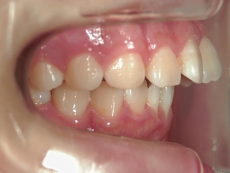

● ツインフォース

下顎が後退している方に用いられる装置です。後ろにずれている下顎を前方(本来の位置)に移動させ、噛み合わせを整えます。

上顎に比べ、下顎が著しく後退しています。

上の歯と下の歯を斜めに繋ぐようにツインフォースという装置を装着します。装置の力で、顎が前方へ押し出されてきました。

顎の移動が終了しました。装置を外して、今後はワイヤーを使用して歯列を治します。

矯正治療後の後戻りを想定して、あえて必要量を越えた顎の移動を行います。